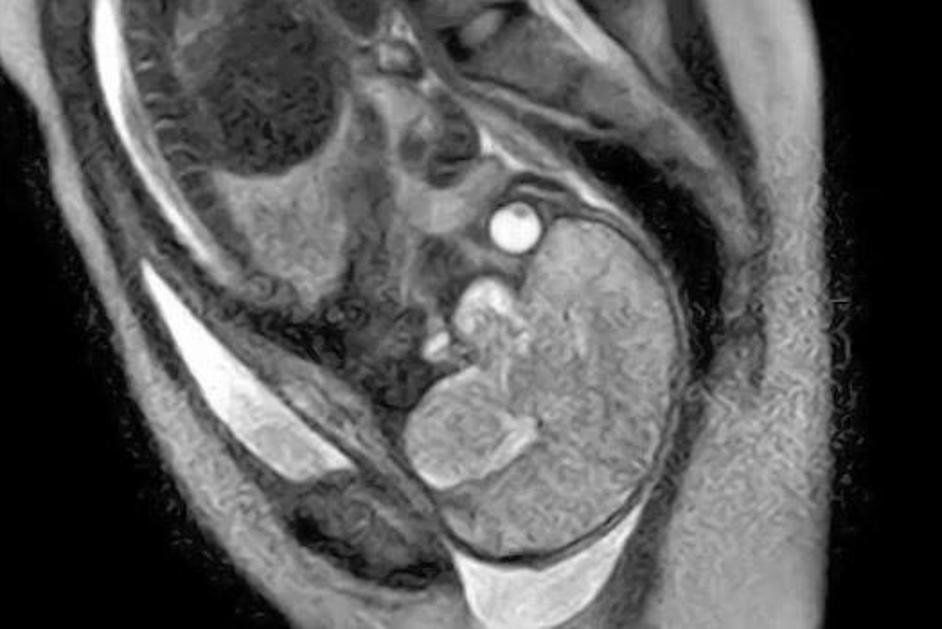

porod, snemanje, magnetna resonanca Sprednji pogled glave otroka v medeničnem vratu. Žurnal24 porod, snemanje, magnetna resonanca